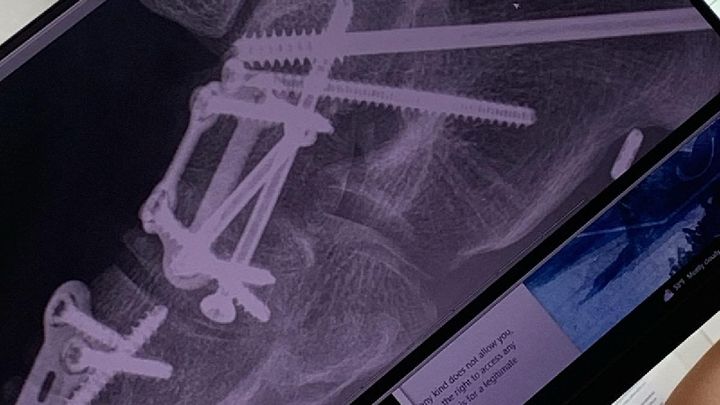

My daughter Maya was born with Cerebral Palsy. When she was younger, she used a walker, but as she got older was able to walk without it. Just like her Dad she's always been very independent, and strong willed. If you told her she couldn't do it, then she was just more determined to show you she could. She refused to get SSI, and was determined to make her own way in life. She got a job, got her own apartment, and furnished it the way she wanted it furnished. As much as I offered, she would never let me buy her anything unless it was her birthday or Christmas. Well starting last July, she was in so much pain walking, that they had to do reconstructive surgery on both her feet. She lost her job, and apt. Now she's in a wheelchair learning how to walk again. We currently have her in a hotel while im working overseas until I can get back, and find her a place to stay. I had her applied for SSI so she can get some type of income, and amazingly, she was denied. I'm over the moon pissed off. How do you deny someone who was born disabled disability??!!?? I know people who are perfectly fine that get disability, and someone who was born with cerebral palsy, is in a wheelchair, and cannot walk is denied because the doctor says she MIGHT be able to walk again in 6-8 months?!? Are you fucking kidding me?!? So what does she do for the next 6-8 months??? So now I have to pay for a lawyer on top of the hotel? Do I have to go John-Q?!!? Currently my ex, her siblings, and me are holding her down but damn, what if she was on her own? I remember when I was living in Brooklyn, Her and her sister came to visit me one summer, and we were at the Saint Marks Church. St Marks had this big step out front, and I could see her out of the corner of my eye. I knew she was going to take that step, and that was ready to catch her. She took it, and I caught her. As long as I'm around, I won't let her fall.